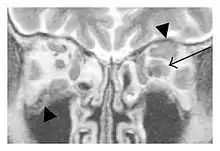

The extent of inflammation that can occur in IgG4-ROD is well demonstrated on magnetic resonance imaging (MRI).

Infraorbital nerve enlargement (IONE) is considered to be a particularly suspicious sign of IgG4-ROD, but seems to occur only when inflammation is in direct contact with the infraorbital canal.[10] IONE is defined as the infraorbital nerve diameter being greater than the optic nerve diameter in the coronal plane.

![]() Swelling of the left superior and lateral rectus muscles, a mass lesion around the left optic disc (arrow), and enlargements of the left supraorbital nerve and the right infraorbital nerve (arrow heads) in a 60-year-old man with a serum IgG4 of 463 mg/dL.[1] (T1-weighted MRI) |

![]() Bilateral supraorbital nerve enlargements (arrows) and right infraorbital nerve (arrow head) enlargement in a 47-year-old woman with a serum IgG4 of 1000 mg/dL.[1] (T1-weighted MRI) |